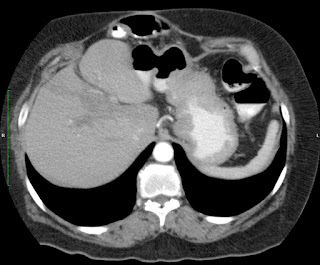

Paciente de 66 años con antecedente de pancreatitis, tomografía control.